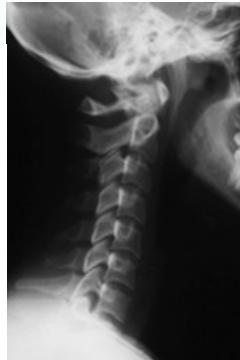

Lateral View

- All C- vertebrae & upper T1

- Prevertebral soft tissue width

- Four parallel curves

- Front of vertebral bodies

- Back of vertebral bodies

- Posterior borders of lateral masses

- Bases of spinous processes